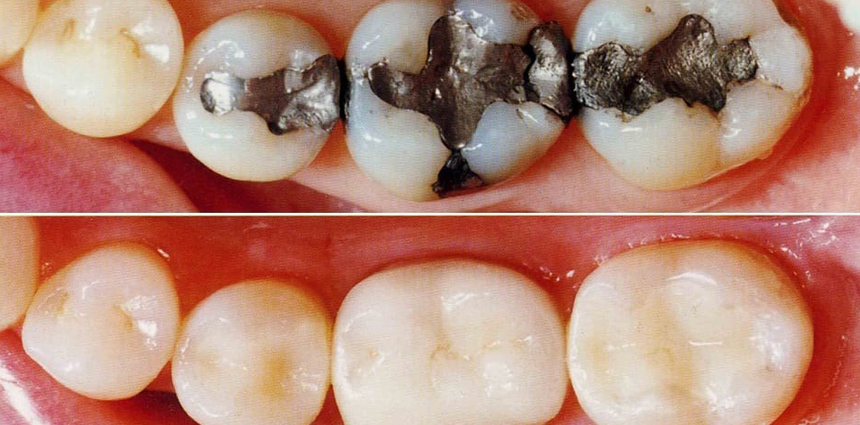

Root canal treatment (RCT)

This is one of the most common procedures for treating the dental pulp in moderate-to-severe cases of tooth decay. The infected tooth is opened up at the crown to provide access to the root canal within. All infected material is removed and once the tooth is clean, the root canal is enlarged so that it can be filled with a temporary dental filling. Once the tooth has healed, this temporary filling is removed, replaced with the permanent filling and the tooth sealed to prevent a recurrence of infection. A crown may be placed over the tooth to protect the tooth from damage.